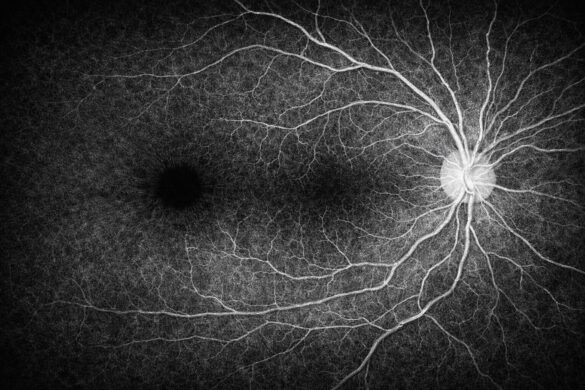

OCT-A(アンギオ)

OCT-Aは、造影剤を使用せずに網膜・脈絡膜の血管構造を描出できる解析機能です。

血管の“形”ではなく“流れの有無”を可視化できるため、虚血・無灌流領域の把握や新生血管の評価に適しています。

層別表示により、どの深さの血管に変化があるかを構造OCTと対比しながら確認できるのが特徴です。